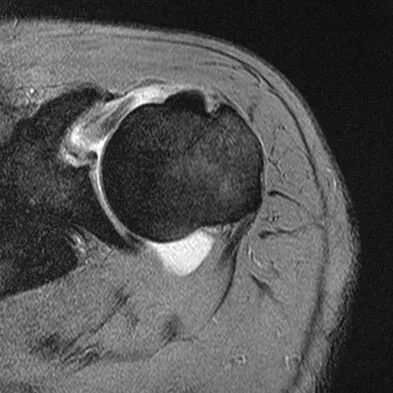

A previously asymptomatic 40-year-old man injures his shoulder in a fall. Examination shows that he is unable to lift the hand away from his back while maximally internally rotated. An axial MRI scan of the shoulder is shown in Figure 14. What is the most likely diagnosis?

Explanation